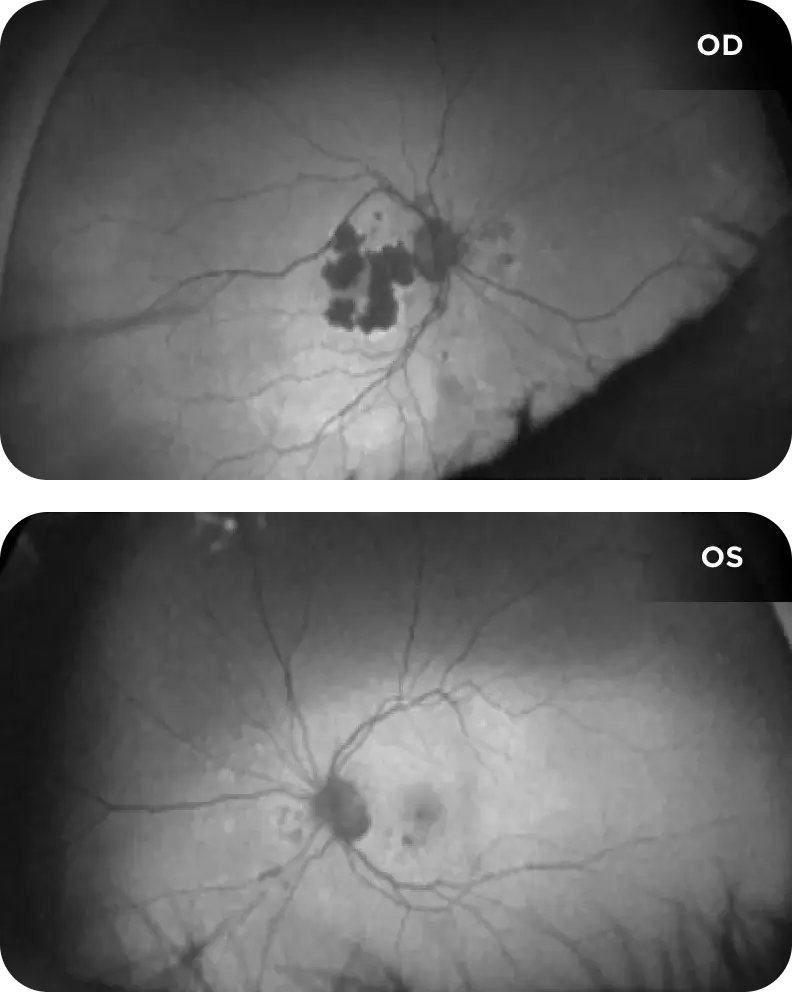

Neovascular AMD

- In clinical trials, use of IZERVAY was associated with increased rates of neovascular (wet) AMD or choroidal neovascularization (7% when administered monthly and 4% in the sham group) by Month 12. Over 24 months, the rate of neovascular (wet) AMD or choroidal neovascularization in the GATHER2 trial was 12% in the IZERVAY group and 9% in the sham group. Patients receiving IZERVAY should be monitored for signs of neovascular AMD.

IZERVAY™ (avacincaptad pegol intravitreal solution) is indicated for the treatment of geographic atrophy (GA) secondary to age-related macular degeneration (AMD)